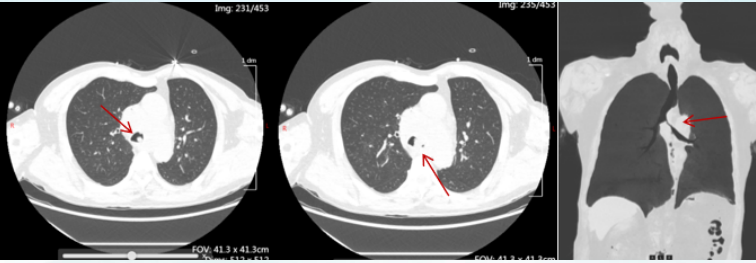

患者男性,56岁,确诊气管腺样囊性癌2年,气短3天。胸部CT提示气管声门下2 cm处狭窄(图4),最窄处4.6 mm。

图片

4  患者胸部CT

患者男性, 61岁, 确诊气管腺样囊性癌8年, 气短加重2月余, 端坐呼吸。胸部CT提示气管下段狭窄(图11), 最窄处4 mm。

11  患者治疗前胸部CT

患者男性,56岁,因“咳嗽、咳痰、气短20天”入院,端坐呼吸状态。胸部CT提示隆突处气管狭窄(图14),左主支气管最窄处1.8 mm。

14  患者治疗前胸部CT